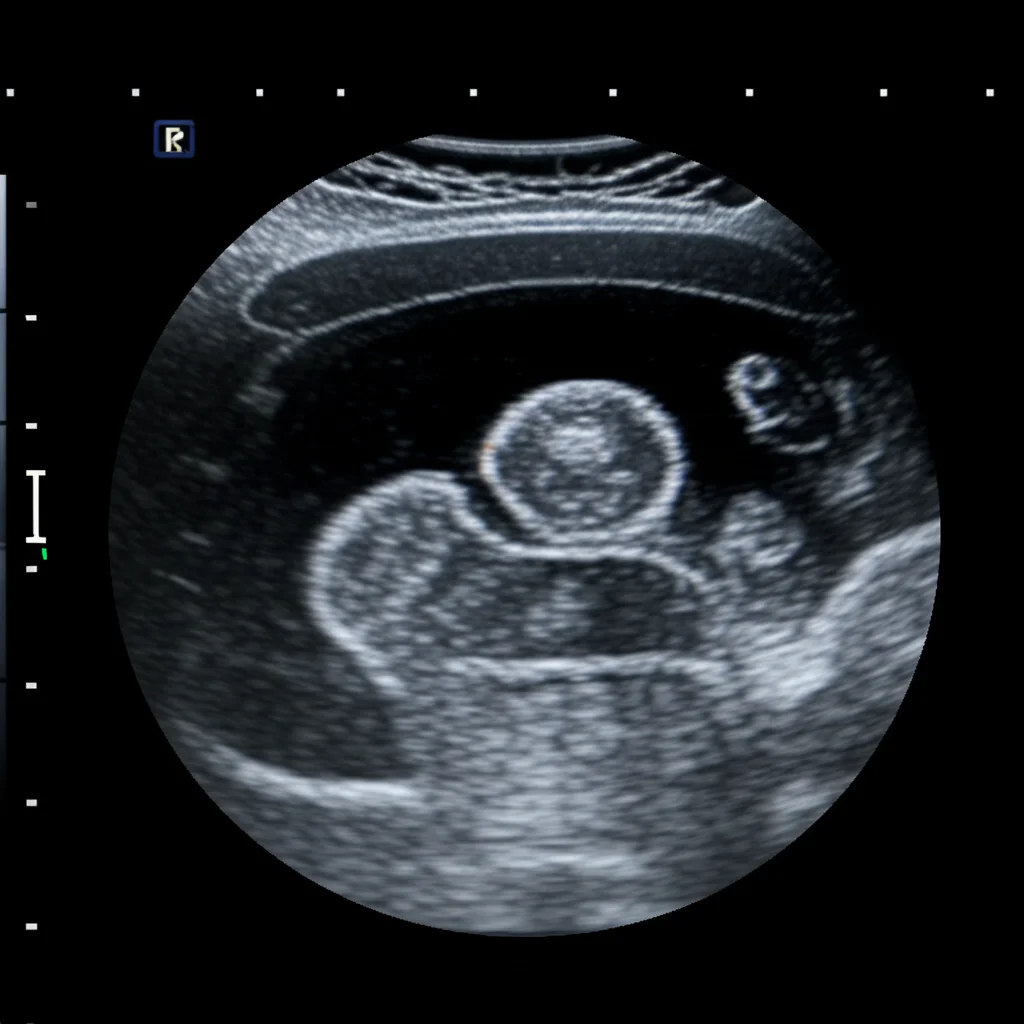

That’s where the **Tiger Model** comes in. Think of it as a special kind of AI that can create images based on text descriptions. We fused clinical insights – all those specific details about how a rare thyroid nodule might appear (its shape, texture, edges, location, etc.) – with powerful image generation technology, specifically diffusion models.

The goal? To produce synthetic ultrasound images that are so realistic and diverse, they can effectively teach AI models to spot these rare subtypes, even when real-world data is limited.

A clever part of the Tiger Model is how it handles the image. It uses separate components (encoders) to focus on the nodule itself (the “foreground”) and the surrounding thyroid tissue and neck structures (the “background”). This allows for really fine-grained control over the generated image details, making them much more convincing and clinically accurate. We used things like segmentation masks to tell the model exactly where the nodule is and edge detection (like a digital sketch) for the background structure.